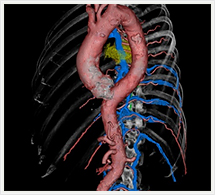

画像紹介

CTでは輪切り像の他にも立体的な画像(3D画像)を作成することもできます。そのためにはより細かくキレイな画像を撮影しなければなりません。当院では64列CTを導入しており、キレイな画像をより細かく撮影することができます。その画像を元に3D画像を作成することによって、より正確な手術のシミュレーションが可能になります。実際に手術をしたときの様子が、手術をする前に画像として見らます。外科系の手術には欠かせない技術となっておりますが、内科系でも血管内手術にも多く利用されております。

当診療放射線技術科では毎日各診療科に対して、その手術に最適な3D画像を提供しております。

以下にその3D画像を一部分紹介します。

胸部大動脈

胸部大動脈(赤)、奇静脈(青)、脊椎結核(黄)